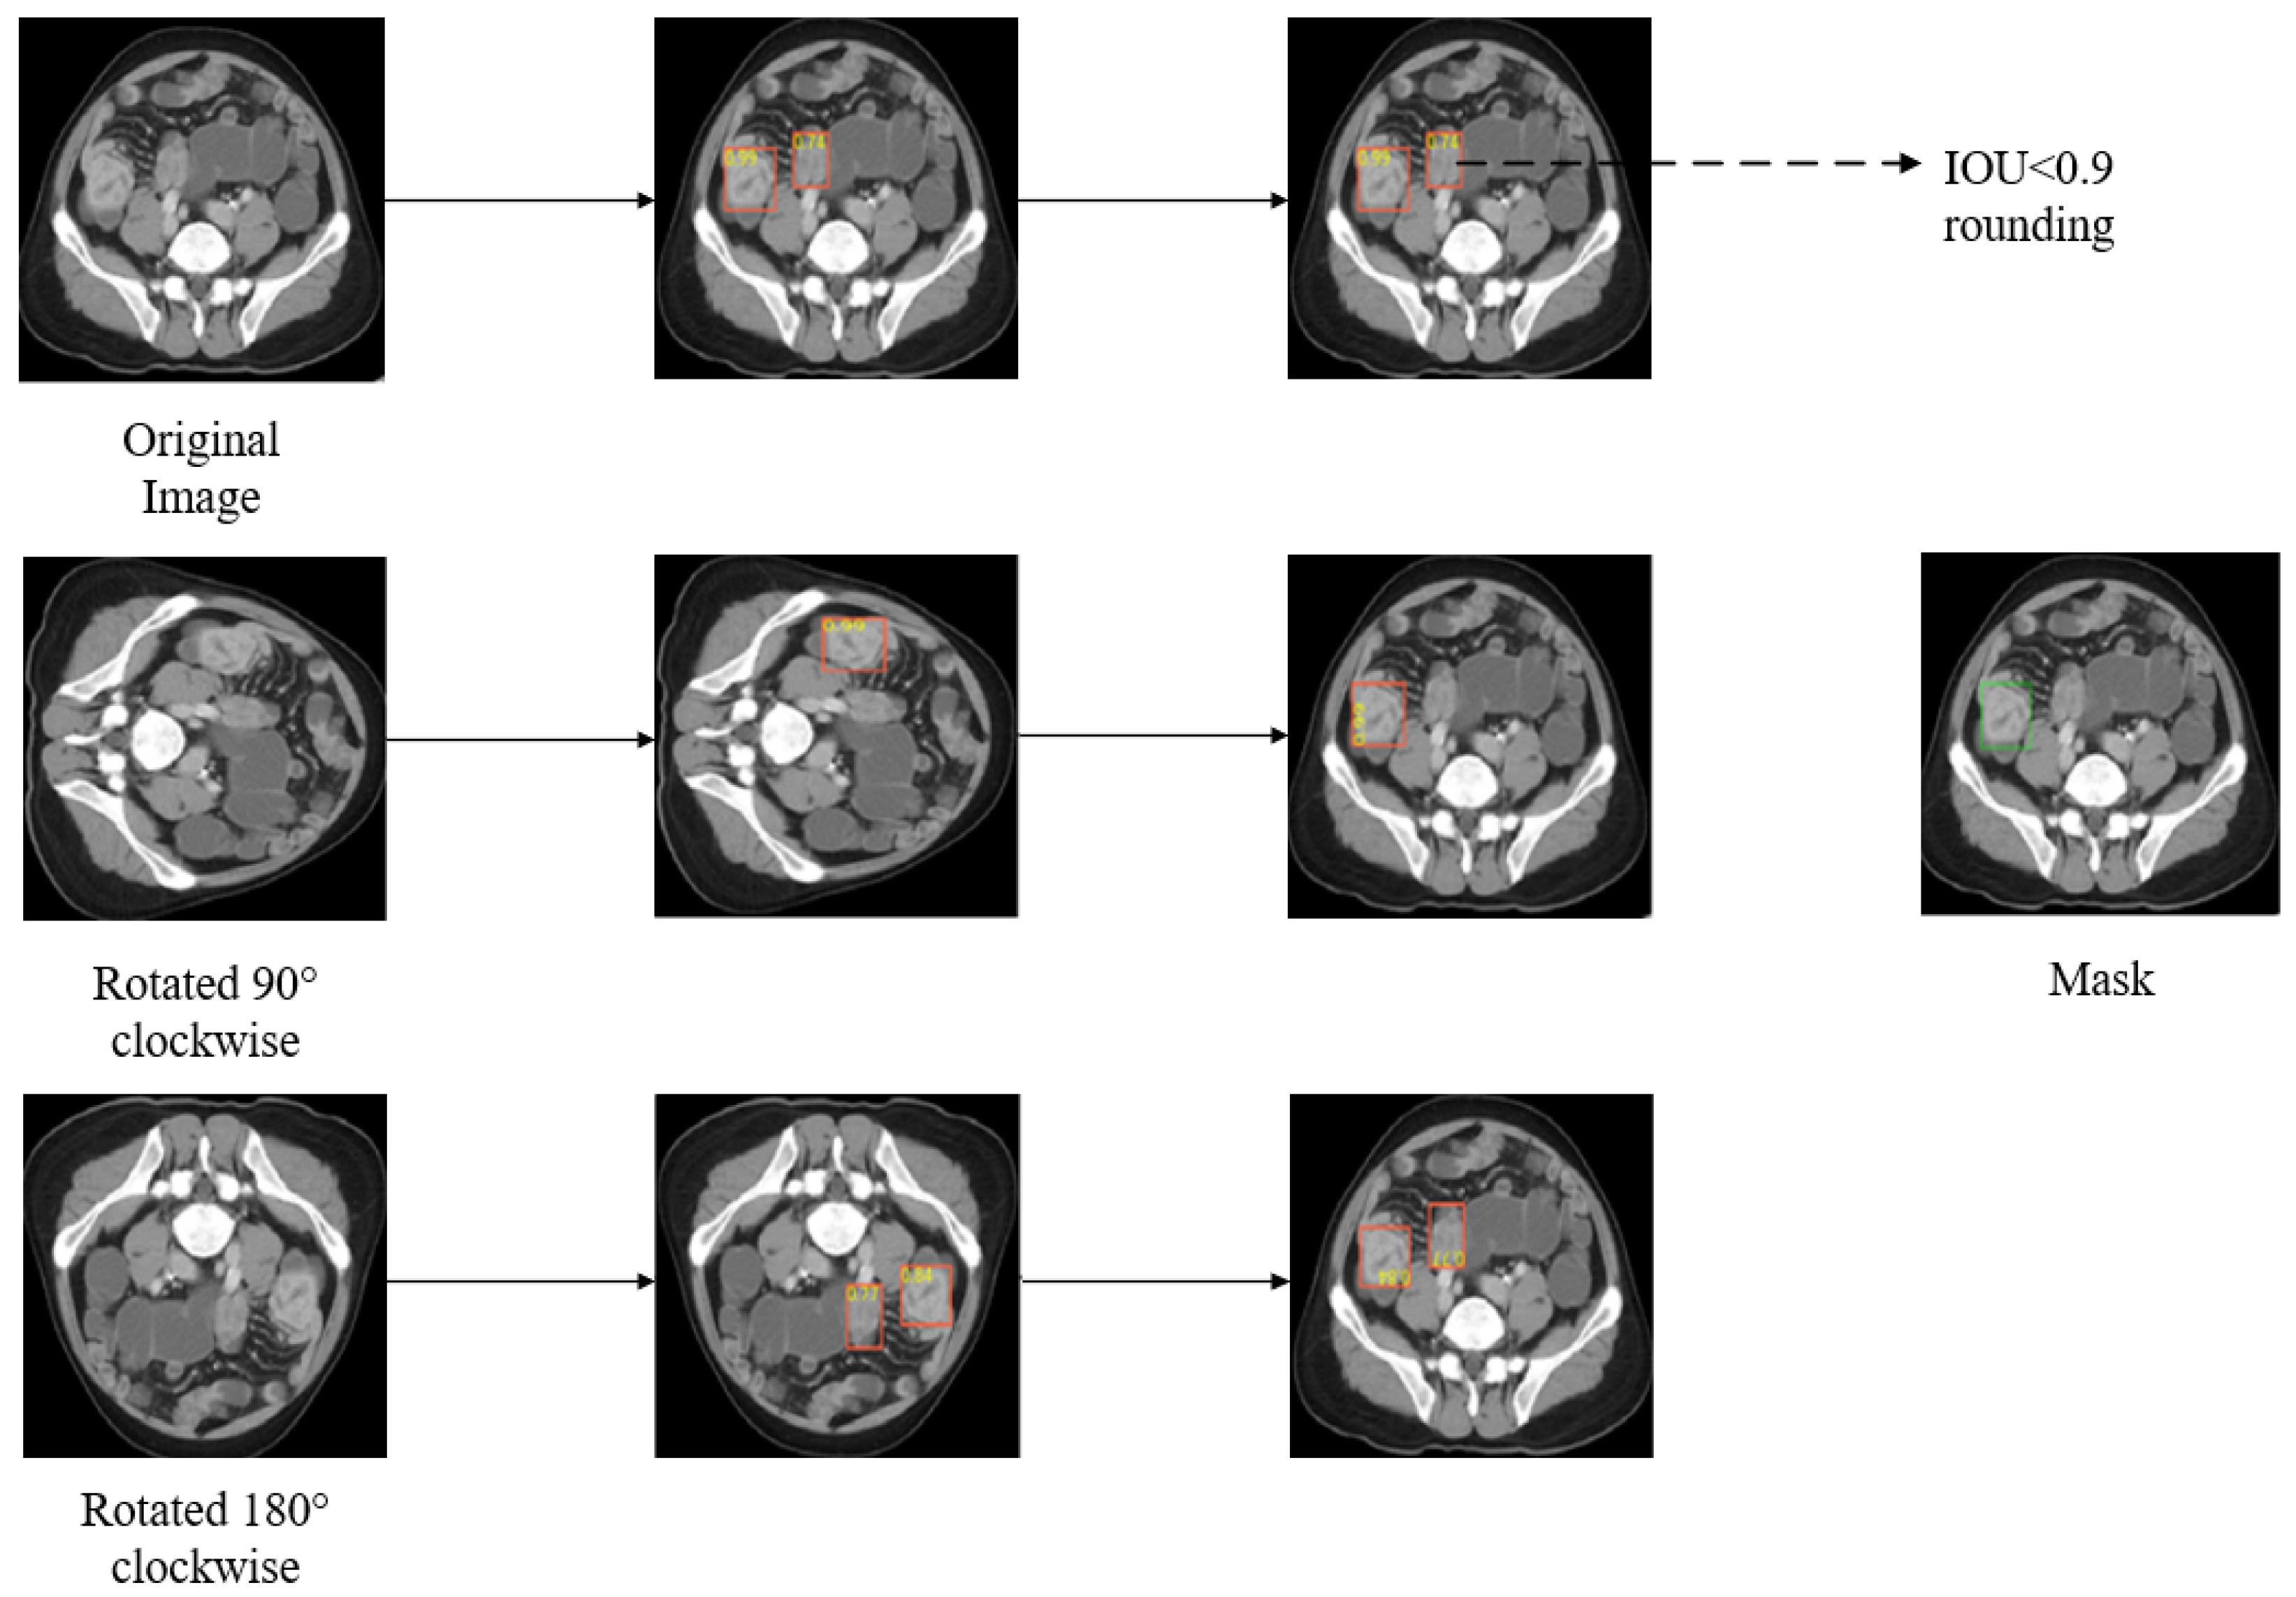

Based on the dynamic threshold, we created a new IOU constraint. The IOU constraint sets the condition for the retention of pseudo-labels. Only when the IOU between the detection results of various transformed images is higher than 0.9 do we regard the bounding box as the pseudo-label. Figure 3 shows the results after applying the IOU constraint. By comparing the original results with the true label, it can be found that the detection box on the right is a false-positive example, which will affect the optimization of the model if it is kept as a pseudo-label. After the IOU constraint is applied, the false-positive bounding box can be successfully excluded, which further ensures the quality of the pseudo labels.

Figure 3. The effect of IOU constraint (the orange bounding box in the figure represents the predicted box, and the green bounding box represents the actual labeled box).